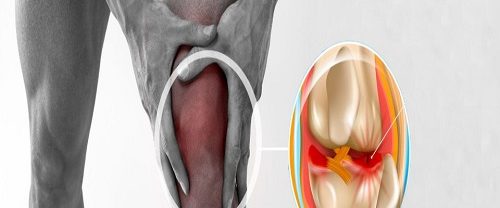

Transfix Tekniği ile Ön Çapraz Bağ Yırtılması ve Tedavi Yöntemleri Transfix Tekniği | Ön çapraz bağ yırtılması, genellikle spor yaralanmaları veya ani dönme hareketleri sonucu ortaya çıkan bir durumdur. Bu yırtık, dizin stabilitesini etkileyebilir ve günlük aktivitelerde ve spor yaparken ağrı ve kısıtlılığa neden olabilir. Ön çapraz bağ yırtılması olan birçok kişi için cerrahi müdahale gerekebilir.…

Menisküs Yaralanmaları ve Onarımı Kelebek Tekniği ile Menisküs Onarımı | Menisküsler, diz ekleminde bulunan kıkırdak yapılar olarak bilinir. Bu yapılar, dizin stabilitesini sağlamak ve darbe emici bir yastık görevi görmektedir. Ancak, spor aktiviteleri, ani dönüşler, yüksek darbe alımı gibi durumlar menisküs yaralanmalarına yol açabilir. İşte menisküs yaralanmaları ve onarımı hakkında daha detaylı bir bakış: Menisküs…